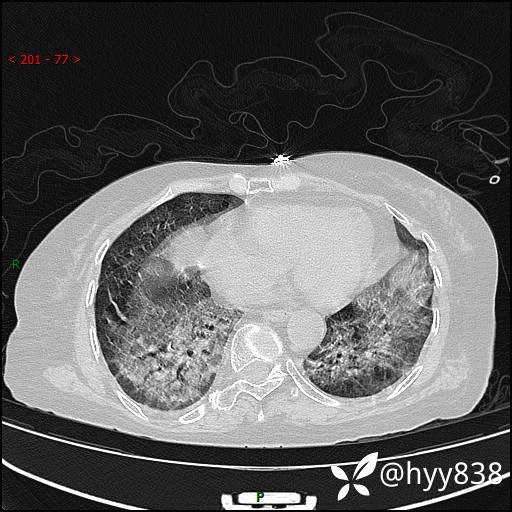

弥漫性肺部病变,辗转当地多家医院未能确诊,拟诊“重症肺炎”入我院--结果公布

患者年龄:69岁

简要病史: 患者20余天前无明显诱因出现发热,最高体温37.5℃,伴头晕,乏力,纳差等不适,无鼻塞,流涕,无咳嗽咳痰,无呼吸困难,无恶心呕吐、关节疼痛等不适,于当地市多家医院就诊,未明确病因,2023.6.23于当地第二人民医院就诊,完善胸部CT示病毒性肺炎,予以抗感染、清热解毒后症状较前稍好转,2天前患者无明显诱因出现活动后喘息加重,伴肌肉酸痛,口干,无明显咳嗽咳痰,今日体温38.1℃,为求进一步诊治来我院就诊,门诊以“ 重症肺炎 I型呼吸衰竭”收入院。 患者起病以来,精神、睡眠、饮食欠佳,大小便正常,体力下降,体重无明显改变。

辅助检查:CT

临床诊断:重症肺炎

胸部CT薄层扫描